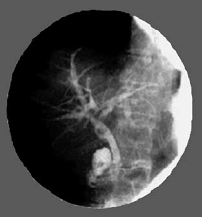

Основой рентгеноэндоуринальных манипуляций чаще всего является чрескожная пункция и катетеризация почечной лоханки при непроходимости мочеточника. Таким путем проводят манометрию и контрастирование чашечно-лоханочной системы (антеградную пиелографию), вводят лекарственные вещества. Через искусственно созданную нефростому производят биопсию, рассечение стриктур мочеточника и его баллонное расширение. Заслуживают внимания дилатация и эндопротезирование уретры при аденоме предстательной железы и аналогичные манипуляции при стриктуре шейки матки.

Эндоурологические вмешательства - это интервенционные лечебные и диагностические манипуляции, проводящиеся под рентген - телевизионным и/или эндоскопическим контролем, производящиеся из перкутанного (чрескожного) или трансуретрального (через мочеиспускательный канал) доступов.

Стентирование мочевыводящих путей